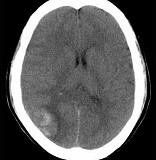

[单选题]男,37岁,头痛、头晕1年余,加重3天,CT检查如图所示,最可能的诊断为()A .脑出血B .脑血管畸形并出血C .脑膜瘤并出血D .颅内动脉瘤E .转移瘤并出血